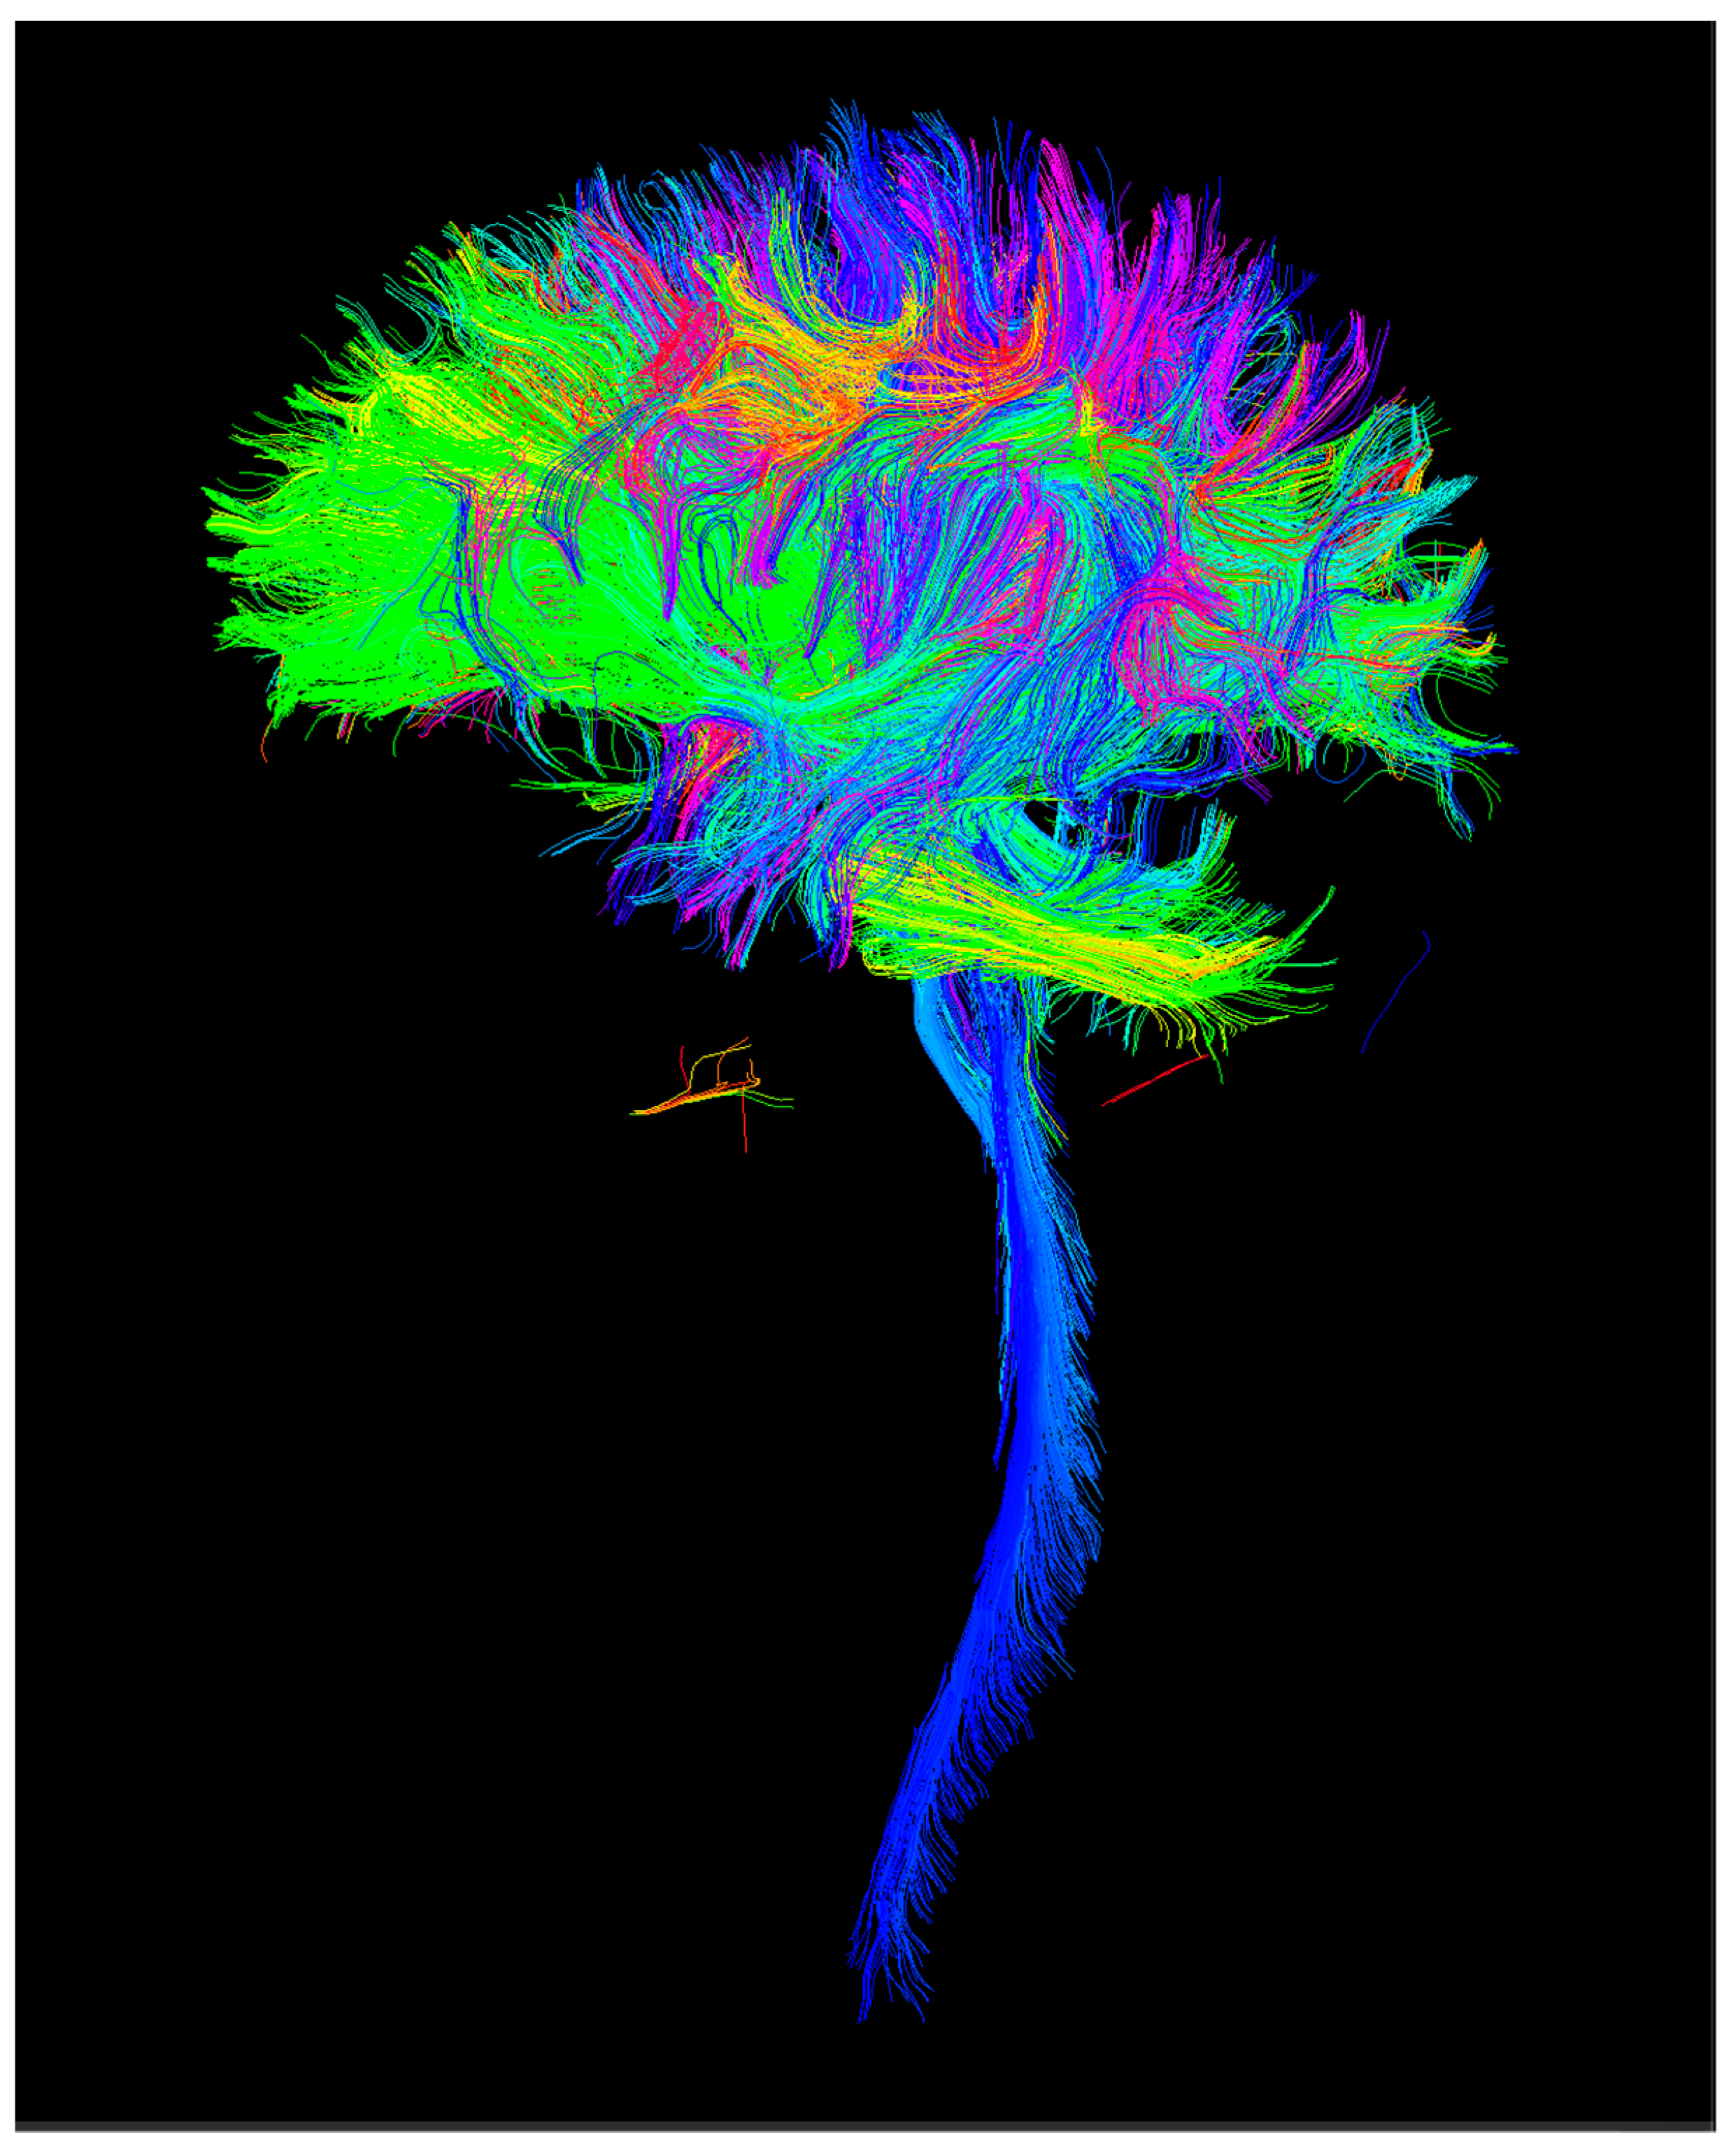

2.1.1. Image Processing

2.1.2. Connectomics